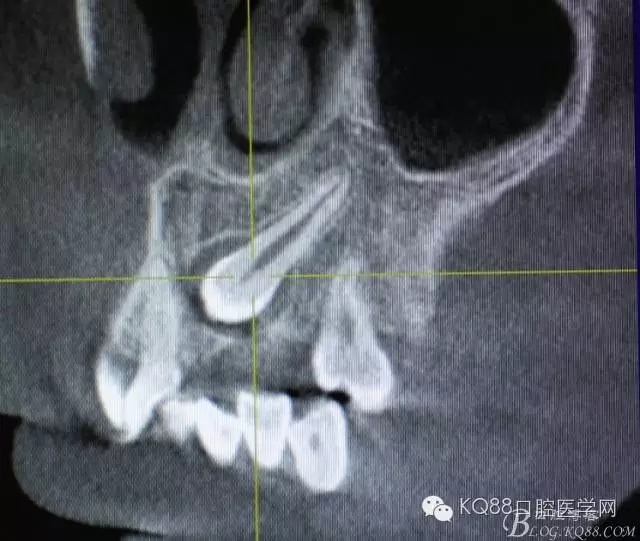

圖3.冠向切面:23牙冠緊鄰21的牙根